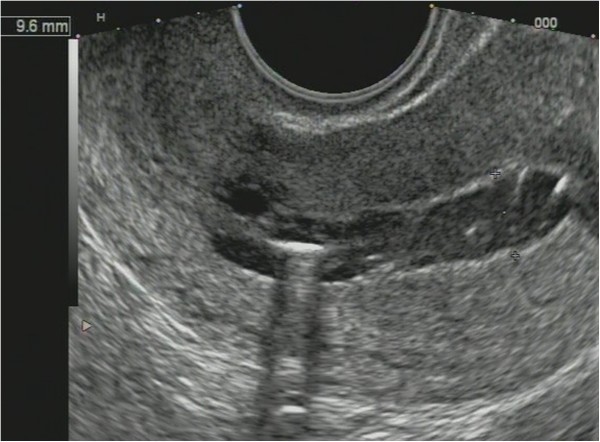

Non-homogenous and irregular margins were significantly higher in AEH than in both groups (P < 0.01). Mean M-echo thickness was found to be non-significant. Hypoechoic areas, hypervascularity on Doppler imaging, and stiffness (Figures 14 and 15) were more specific for AEH than for glandular cystic hyperplasia (P < 0.01, P < 0.01, P < 0.01, respectively; Figure 16). Fluid in the uterine cavity and BGR artefact were found to be specific for AEH (P < 0.01; Figure 17); BGR appearance correlated to the presence of fluid in the uterine cavity (r > 0.97; Figure 18).

Figure 14

Endometrial polyp ( P ). (A) Stiff polyps on SEG, arrow indicates invisible polyp in grey scale that was detected on SEG; (B) Dopplerography of polyp vessel, RI = 0.7.

Figure 15

Sonoelastography of endometrial lesion. Soft pattern on SEG helps to exclude the polyp.